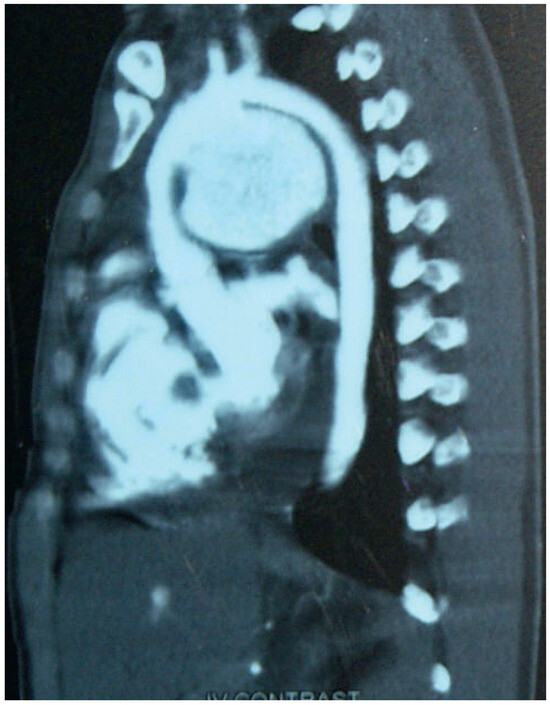

Surviving Acute Traumatic Transection of the Ascending Aorta and Proximal Aortic Arch

We report a 22-year-old male patient who survived clinically unapparent acute traumatic transection of the distal ascending aorta and the proximal aortic arch. Two months after the incident, the patient presented with hoarseness, respiratory distress and severe venous congestion of the upper part [...] Read more.

We report a 22-year-old male patient who survived clinically unapparent acute traumatic transection of the distal ascending aorta and the proximal aortic arch. Two months after the incident, the patient presented with hoarseness, respiratory distress and severe venous congestion of the upper part of the body. Echocardiography demonstrated a huge mediastinal tumour, dilated right heart chambers as well as pericardial tamponade. In the computed tomography (CT), scan rupture of the distal ascending aorta and the proximal aortic arch was found. The preserved adventitial layer, preventing immediate death from exsanguination or pericardial tamponade, distended over time forming a false aneurysm with a diameter of 9 cm, with its main part being located to the left of the trachea. Systolo-diastolic motion of the thin-walled false aneurysm led to the typical pulse-synchronous horizontal motion of the thyroid cartilage and the trachea, described as the Cardarelli sign. As a result of systolic expansion and diastolic shrinking of this huge false aneurysm, the arterial blood pressure curve of the patient perfectly imitated the blood pressure curve seen only with a properly timed intra-aortic balloon pump. In addition, the systolic blood pressure repeatedly compressed the main pulmonary trunk, which crossed the bottom of the false aneurysm, consecutively leading to clinically apparent right heart failure, serous pericardial effusion and pericardial tamponade. The patient successfully underwent ascending aortic and proximal aortic arch replacement using deep hypothermia, circulatory arrest and selective antegrade cerebral perfusion. Full article

Show Figures

Figure 1